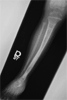

Progress

Child walking full-weight bearing with ankle straightened and lengthening tibia completed